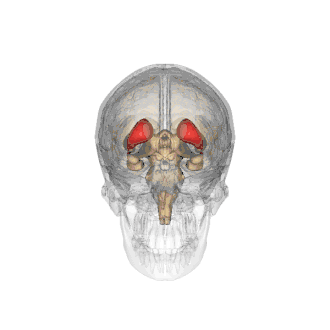

De nucleus caudatus in het rood aangegeven.

De nucleus caudatus[2] of staartkern[3] (Latijn: nucleus = kern; cauda = staart[4]) is een van de structuren van het corpus striatum in de hersenen van de mens en veel diersoorten. Lange tijd werd gedacht dat deze structuur, die deel uitmaakt van de basale kernen,[5] uitsluitend betrokken is bij de regulatie van motorische processen. De nucleus caudatus lijkt bij mensen met de ziekte van Parkinson, een bewegingsziekte, niet langer te worden geïnnerveerd door de pars compacta substantiae nigrae.[6] Uit recentelijk onderzoek blijkt echter dat de staartkern daarnaast ook een belangrijke rol speelt bij het leren en herinneren, met name voor het verwerken van terugkoppeling. Verder maakt de nucleus caudatus deel uit van het beloningssysteem van de hersenen en van de cortico–basale ganglia–thalamische lus.[5]

Anatomie